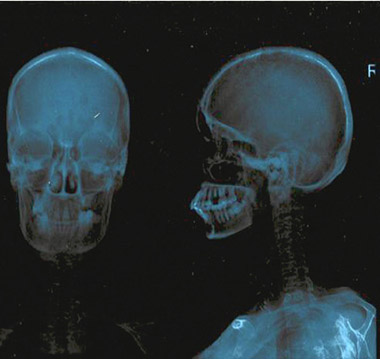

The patient had suffered trivial trauma to hip when she fell down in bathroom 3 months prior to presentation and she has been wheelchair bound since then. She was initially evaluated at a private hospital and was diagnosed as a case of pathological fracture of neck of left femur. Initial X-Ray skull, pelvis and LS spine revealed salt and pepper appearance, osteopenia with osteophytes and decreased L3‒L4 & L4‒L5 disc spaces (Figures 1A, 1B).

A. Salt pepper appearance of skull |

B. Multiple osteolytic lesion in skeletal bones, pelvis and LS spine |

Figure 1. |